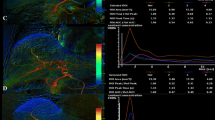

The paired comparison allowed a side-by-side evaluation of DSA and DVA images in a blinded and randomized manner. DVA was the preferred image in 80% of comparisons (Fig. 4, left panel), and the average score (mean ± SEM) of the whole image set was 1.44 ± 0.21, the median score was 1.60 (IQR 2.4), significantly different from 0 (one-sample Wilcoxon p < 0.001), which represented the equal quality level, indicating the superiority of DVA images (Fig. 4, right panel). The interrater agreement was also significant (Kendall’s W value: 0.575, p < 0.001). Representative image pairs are shown on Fig. 5.

Paired comparison of DSA and DVA images. Readers compared the image quality and diagnostic value of image pairs in a blinded, randomized manner, and expressed their image preference using a 5-grade preference scale. The left panel shows the distribution of the average preference scores of individual image pairs. The box and whiskers plot shows the mean (x), median (line), interquartile range (box) and internal fences (whiskers) of the complete image set. The 0 line represents the theoretical equal quality level. Data were analysed by the one-sample Wilcoxon test (***p < 0.001). DSA: digital subtraction angiography and DVA: digital variance angiography

Comparison of a representative DSA (left panels) and DVA (right panels) image pairs. More millimetre to submillimetre arterial vessels can be depicted on the DVA images, and both the lesions and the feeding arteries can be evaluated more clearly. The DSA and DVA images were generated from the same unsubtracted image series using the Siemens Syngo or the Kinepict Medical Imaging Tool software, respectively